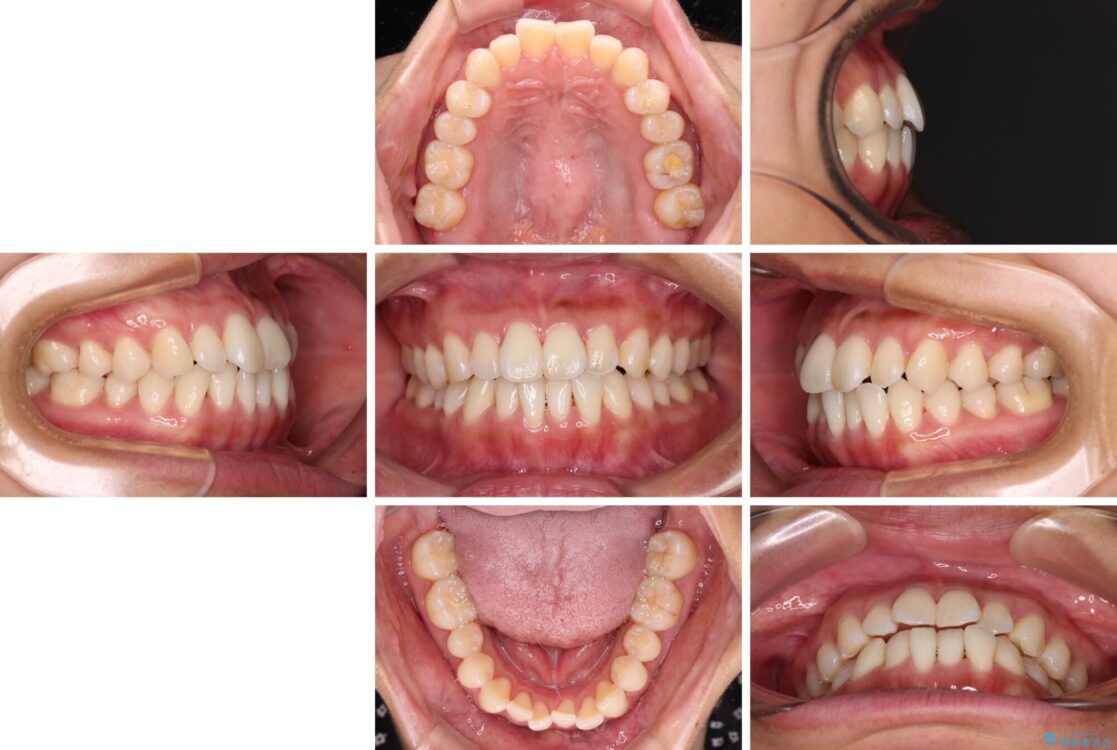

前歯のデコボコで前方に出ていることを気にして来院された患者様です。

上顎前歯が捻れて前方に飛び出しており、下顎前歯もそれに沿うようにデコボコとなっていました。

治療前

• 【モニター】前歯のデコボコをインビザラインで改善 治療前画像